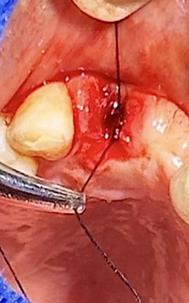

Sindesmotomía con un periostótomo de molt # 9, posteriormente se realizó la luxación con un elevador recto, buscando el punto de apoyo, seguido se efectuó la prensión con el fórceps 150 en el diente con sumo cuidado de no tocar la encía colocándolo hasta el cuello dental, haciendo movimientos de lateralidad y rotación hasta lograr la dilatación del alveolo, y finalmente la tracción del órgano dentario, observando que la raíz este integra, y que estructuras alrededor estén conservadas, de la misma forma se revisó el alveolo en busca de la presencia de granulomas o espículas óseas, una vez ya revisado se procedió al curetaje, con una cucharilla de lucas, se introdujo y se dio paso al retiro del exudado purulento, se realizó irrigación del alveolo con solución fisiológica, una vez limpio se realizó una sutura simple con sutura nylon, seda # 3/0 en el medio del alveolo con la finalidad de aproximar rebordes, evitar su contaminación por el ingreso de comida, además generar una mejor cicatrización en una zona estética , finalmente se aplicó presión por medio de una gasa que mordió el paciente por un lapso de 30 minutos, para contribuir con una hemostasia adecuada.

Figura 7. Exodoncia de la unidad dental, revisión del alveolo, curetaje y retiro de exudado purulento con cucharilla de lucas.

Elaboración: Los autores.